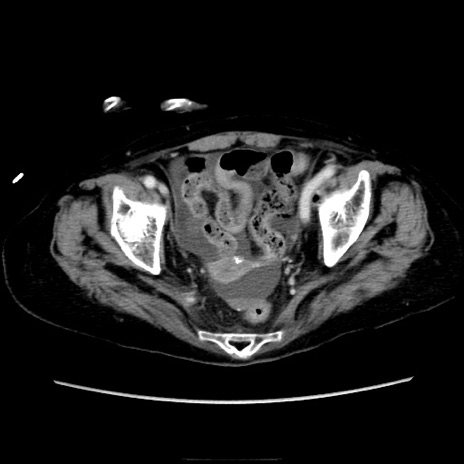

症例40(横断像)

【症例】90歳代女性

【主訴】腹痛・嘔吐

【現病歴】 食欲低下、嘔吐があり昨日他院受診。肺炎と診断され入院となる。入院後より腹部全体に圧痛あり。胃管留置され経過みていたが、症状持続するため、

当院転院となる。

【既往歴】胸椎圧迫骨折、胆石症

【身体所見】腹部:中央に激痛あり、圧痛あり、反跳痛不明

【データ】WBC 17100、CRP 18.82

横断像